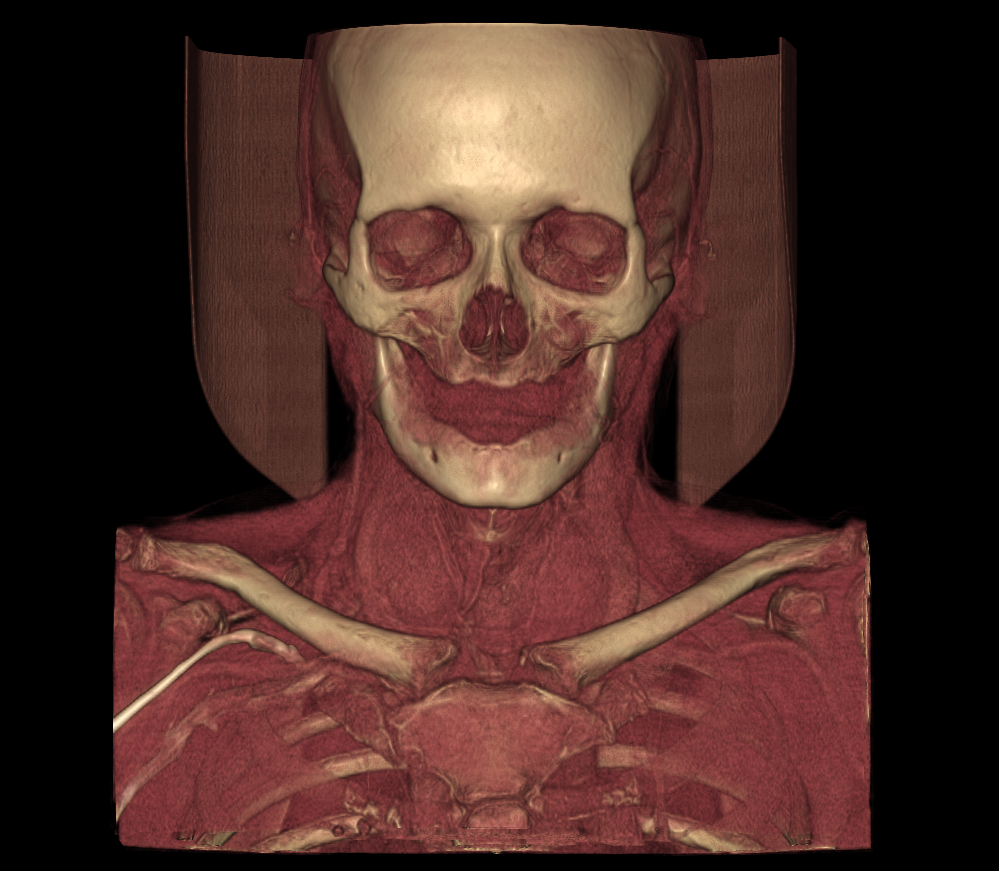

Todo lo que necesita

Herramientas avanzadas diseñadas para profesionales médicos.

Resultados y análisis instantáneos para una toma de decisiones más rápida y un flujo de trabajo mejorado.

Véalo en acción

Experimente el poder de nuestra plataforma a través de estas demostraciones interactivas.